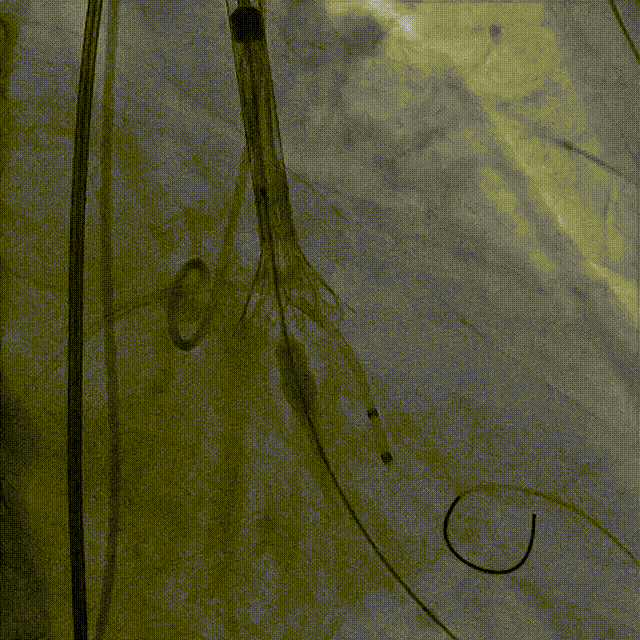

术中影像

直头导丝跨瓣

释放